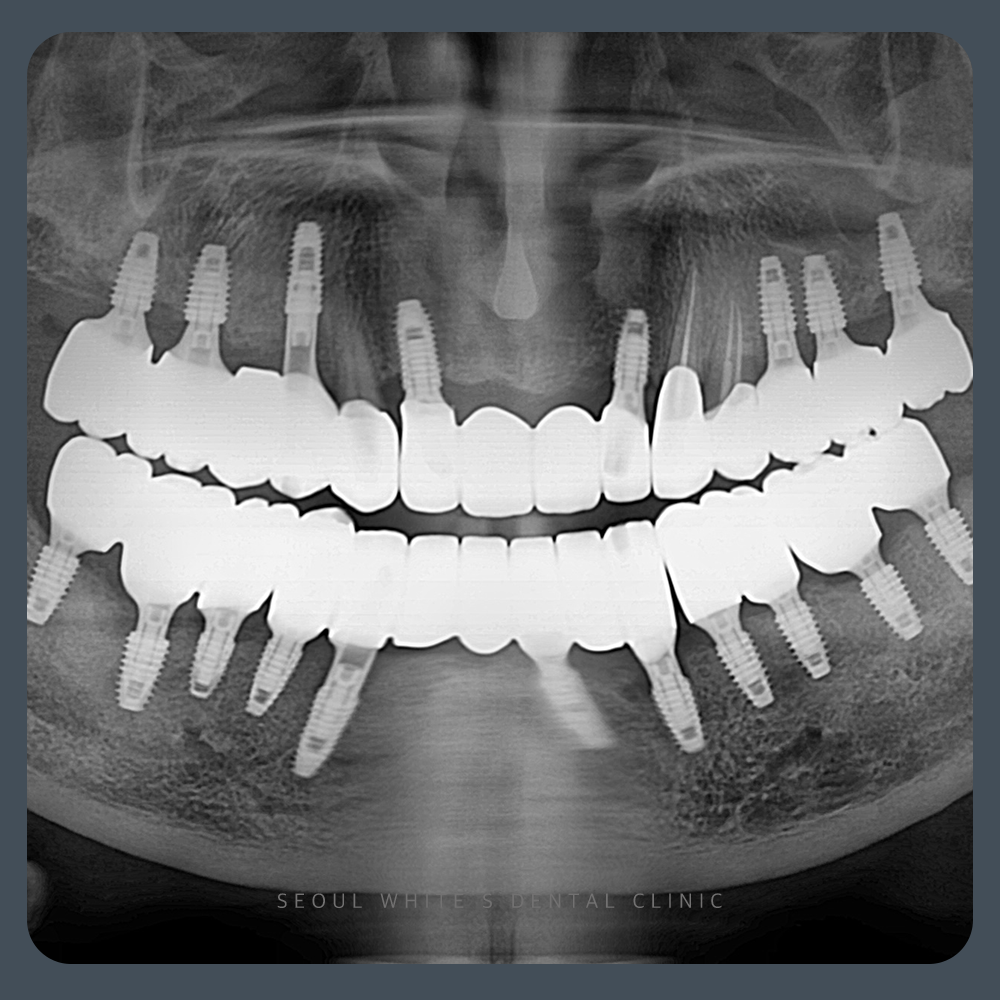

2024.10.14

충분한 회복 기간을 거친 후 임플란트를 식립했습니다. 이전보다 안정적인 골 높이가 확보되었고, 정상 수준과 유사한 골 구조가 형성되어 임플란트 사용에 문제가 없을 정도로 회복되었습니다. 물론 깊은 병소가 있었던 부위는 완벽히 회복되긴 어렵지만, 임플란트의 장기적인 사용에는 무리가 없을 정도의 결과였습니다.

골이식 직후 서둘러 임플란트를 심으면 실패 확률이 높아질 수 있습니다. 그러나 충분한 시간과 과정을 거쳐 치료를 진행한다면, 뼈의 안정성을 확보할 수 있고 그만큼 환자분의 만족도도 높아집니다. 이러한 판단은 단순한 임플란트 경험만으로는 어렵습니다. 다양한 골이식 경험과 치주질환에 대한 깊은 이해가 있어야만 가능한 부분이며, 치료 과정에 대한 환자분의 이해와 신뢰 또한 매우 중요합니다.